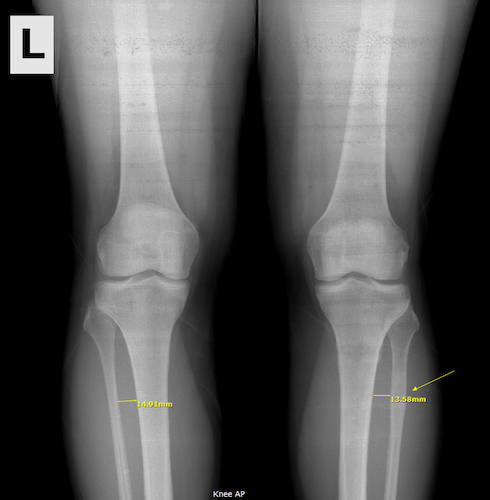

In the summer of 2012, I was diagnosed with a stress fracture near the top of my right fibula (the smaller leg bone under the knee). The X-rays showed a lot of swelling around the bone, and my doctors estimated that I’d had the stress fracture for about nine months. !!! I can pretty much pinpoint the day it happened. I was jogging slowly down a hill in those same crap shoes that had caused my shin splints when I first attempted the C25K, and suddenly my leg went numb from the knee down. There was no pain or anything, and I walked the rest of the way to the car. I went home and sat down and did some icing. It took about four hours for the numbness to disappear. I didn’t think much more about it a the time, but I’ll bet that’s when the fracture occurred. I ended up having to stop all exercise in my lower body (even walking) for 12 weeks that summer.